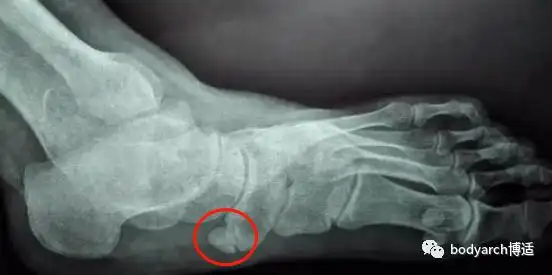

带您了解足"副舟骨"综合征

足副舟骨(即足舟骨之子骨)是舟状骨结节部第二化骨中心的先天性变异.

患者主诉:患者为扁平足,双足副舟骨且足部疼痛.